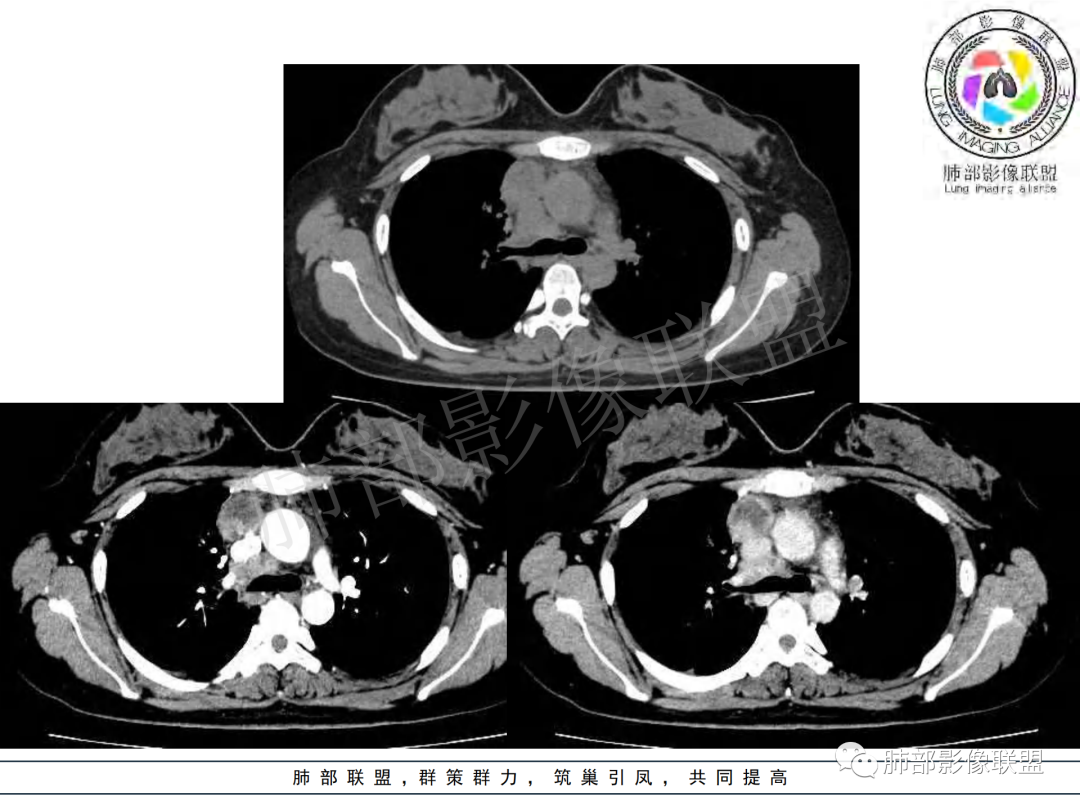

纵隔多组及右侧肺门多发肿大淋巴结,部分融合,不均匀强化,内见斑片状坏死区及环状强化,后者坏死边界尚清晰,肺门区肿大淋巴结与肺组织边界不清,年轻女性,8个月病史,发热首发症状,考虑淋巴结核并向肺内侵及(破溃?),鉴别淋巴瘤

女,20,病程长达8月,发热、胸痛、右侧胸腔积液病史。胸部CT:右肺门旁不规则肿块影,右中间支气管腔内结节,纵隔多发淋巴结肿大;强化不均匀,灶性坏死灶,环形强化;右侧少量胸腔积液并局部肉芽肿样突起。年轻女性,长病程,多部位,考虑慢性炎症,结核?鉴别肿瘤。

年轻女性 大支气管占位恶性三件套 高强化 内部可见无强化区,无强化区与强化区内边界大部分不清晰,类癌、粘表、腺样囊性癌。首先考虑粘表   其次需要鉴别的有结核   这么大片的坏死 结节病可能性小

青年女性,发热、胸痛、右侧胸腔积液病史,病程8个月。曾多次抗炎后均有好转。CT:右肺门旁肿块影,双侧胸膜结节,纵隔多发淋巴结肿大,边缘模糊;增强渐进性明显强化,纵膈淋巴结较彻底坏死灶,边缘环形强化。考虑结核,鉴别恶性肿瘤。

女性,20岁。高热、畏寒。右肺上叶近肺门区不规则肿块,周围斑点、片小结节影伴肿大淋巴结,肿块包绕并突入右主支气管腔内,增强后肿块不均匀强化,淋巴结环形强化中心低密度,考虑结核。

本例患者,年轻女性,慢性病程,多次抗感染治疗效果不佳,实验室检查示白细胞及中性粒细胞不高,不支持普通细菌感染,虽然肺泡灌洗液X-Pert检测阴性,结合患者胸部CT结核感染亦不能排除,胸部CT主要表现为右侧肺门及纵隔淋巴结肿大,仔细观察不难发现右中间支气管内新生物凸向管腔内,增强扫描,右肺门(10R)及纵隔淋巴结(2R,4R)明显不均匀强化,内部呈不规则低密度无强化区,被周边高强化区包绕(环形强化)的特点,首先应当想到纵隔淋巴结结核诊断。淋巴结分布亦不符合肺部恶性肿瘤迁徙途径。